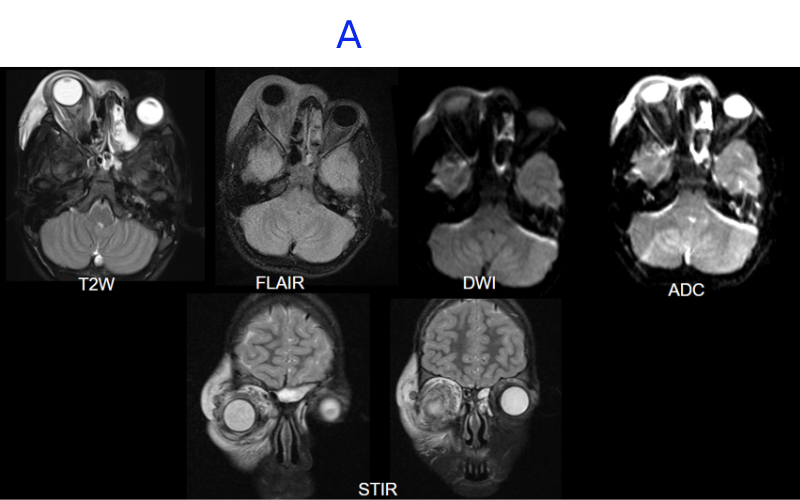

A. FINDINGS – MRI BRAIN WITHOUT IV CONTRAST - DAY 1

A. Right globe proptosis noted . There is extensive T2/STIR hyperintense edema noted in periorbital soft tissue and orbital compartments involving intraconal, extraconal and preseptal space. There is soft tissue stranding involving postseptal fat, surrounding the extraocular muscles and enlargement of lacrimal gland.There is a small diffusion restricting collection along medial wall of orbit. There is thrombophlebitis of an external vein along the superolateral superficial soft tissues.